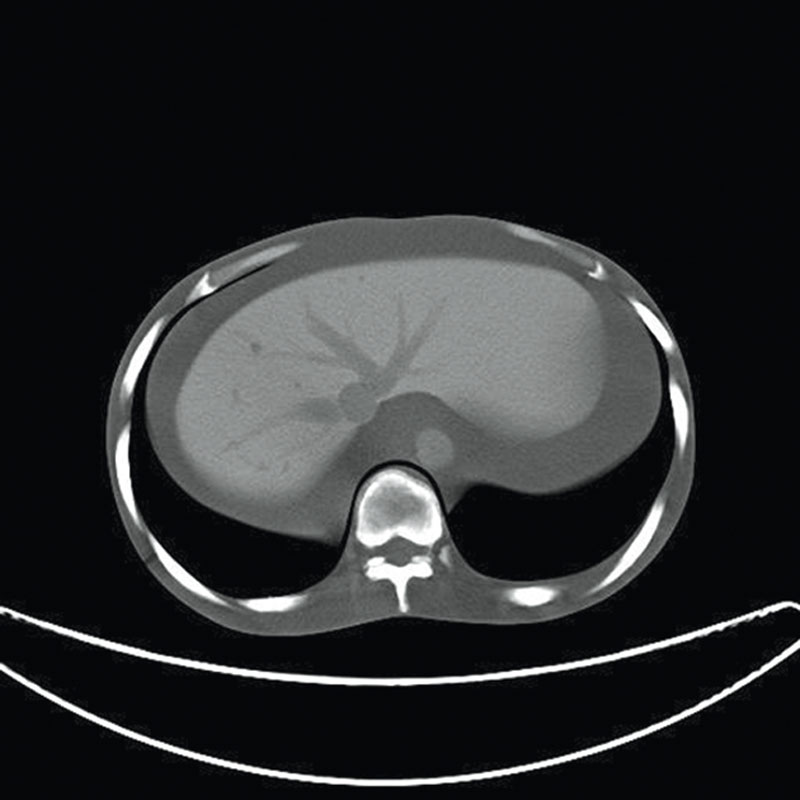

Ein einzigartiges Ganzkörperphantom für CT bietet eine Vielzahl von Ausbildungs- und Forschungsmöglichkeiten. Das Phantom kann auch für normales Röntgen benutzt werden und gibt lebensnahe Bilder. Es benden sich keine Metallteile oder Flüssigkeiten im Phantom. Die wichtigen Gelenke haben eine menschenähnliche Beweglichkeit und erlauben vielfältige Positionen für die Übung. Das Phantom kann in 10 Teile zerlegt werden. Die verbesserten Schultergelenke erlauben es, die Arme nach oben zu bewegen. Die künstlichen Organe sind anatomisch korrekt und haben entsprechende HU-Zahlen.

- Leber mit Pfortader und Lebervene

- Bauchspeicheldrüse

- Nieren

- Gallenblase

- Milz

Radiologische Absorption und Hounsfield-Nummer ähnlich dem menschlichen Körper.